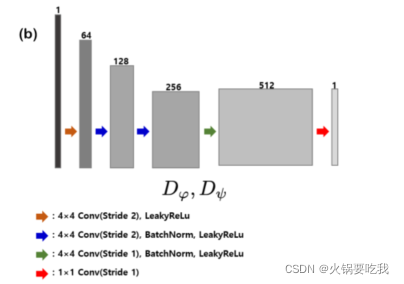

判别器:PatchGAN